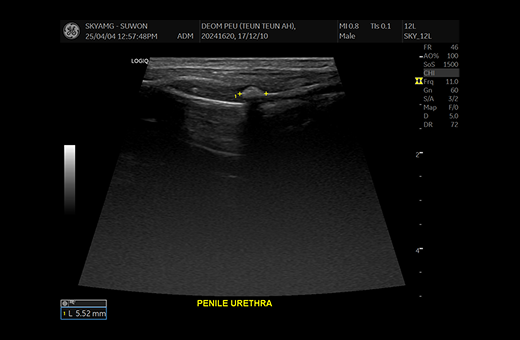

· 초음파 검사

방사선 검사 후, 방광 내부 상태와 요관 상태를 보다 정밀하게 확인하기 위해 초음파 검사 등이 추가로 진행될 수 있습니다.